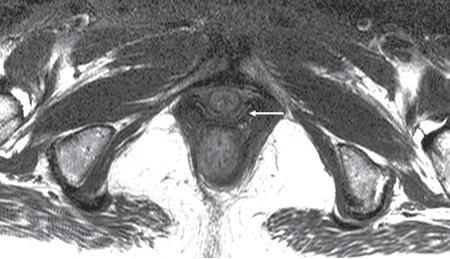

PELVIC FLOOR IMAGING – ANTERIOR AND MIDDLE COMPARTMENTS Anu Epean, Deepa Korula The term ‘Pelvic floor disorder’ refers to dysfunction of the pelvic floor musculature and connective tissues which provide support for the pelvic organs. This can produce a wide range of symptoms such a urinary incontinence, straining to void, dyspareunia, constipation, faecal incontinence and organ prolapse. The greatest risk factors for pelvic floor disorders are female sex and advanced age. Other risk factors include obesity, pregnancy, multiparity, smoking, connective tissue disorders. The pelvic floor is broadly divided into three compartments. The bladder and urethra form the anterior compartment. The vagina and uterus form the middle compartment and the posterior compartment comprises of the rectum and anal canal (Fig. 7.16.1.1). The attachment of the fascia, muscles and the ligaments to the bony pelvis form the support for these structures. From cranial to caudal, there are three layers which make up the pelvic floor – the endopelvic fascia, the pelvic diaphragm and urogenital diaphragm. This is the most cranial layer of pelvic floor, lying deep to peritoneum. It is a fine structure, comprising of a network of connective tissue which encases the pelvic viscera, provides support to the pelvic organs and maintains their anatomic relationship. There are several condensations of this fascia and ligaments which provide support in each of the pelvic compartments. In the anterior compartment, a fascial condensation called pubocervical fascia extends from anterior vaginal wall to the pubis. Tear in the pubocervical fascia can cause cystocele and urinary incontinence. There are three groups of ligaments which provide urethral support – periurethral, paraurethral and pubourethral ligaments. The periurethral ligaments arise from medial fibres of pubococcygeus and pass ventral to urethra. The paraurethral ligaments connect the lateral wall of urethra to periurethral ligament and pubourethral ligament connects the lateral wall of urethra to arcus tendineus. The urethra lies on a Hammock-like supportive layer of endopelvic fascia and anterior vaginal wall, which are stabilized by attachment laterally to arcus tendineus and levator ani (Fig. 7.16.1.2). In the middle compartment, condensations of the endopelvic fascia which attach the uterus to the lateral pelvic wall is called parametrium, which is made up of the uterosacral and cardinal ligaments. The uterosacral cardinal ligament complex supports and suspends the cervix and upper vagina above the levator plate. More inferiorly, the paracolpium attaches the vagina to the lateral pelvic wall. There are three levels of fascial support to the vagina: In the posterior compartment, the perineal body located within the rectovaginal septum supports ligaments and muscles and prevents abnormal widening of levator hiatus (Fig. 7.16.1.3). The rectovaginal fascia extends from posterior wall of vagina to anterior rectal wall. A tear in the rectovaginal fascia is the cause for an anterior rectocele. Arcus tendineus levator ani (ATLA) is formed by the condensation of the endopelvic fascia laterally, along the pelvic sidewall. This extends obliquely from inferior pubic symphysis to ischial spine and provides lateral support to the pelvic organs and attachment of the levator ani. Fascial condensations are not visualized on imaging; however, organ prolapse, due to deficiency in any of these, can be detected on MRI. The levator ani and the coccygeus muscles make up the pelvic diaphragm. The levator ani is the primary muscle of the pelvic diaphragm and is attached to the pubis and to the ATLA laterally on both sides. The slow twitch fibres of the levator ani continuously contract, maintaining tone to the pelvic floor and suspending the pelvic organs in the correct position. The two most important components of the levator ani are the iliococcygeus and puborectalis muscles. The iliococcygeus arises from external anal sphincter and has a curved shape, concave inferiorly. It fans out laterally to its insertion in the posterior part of arcus tendineus (Fig. 7.16.1.4A and B). Posteriorly, in the midline, condensations of ilococcygeus form a firm raphe anterior to coccyx called the anococcygeal ligament or levator plate. The pubococcygeus muscle is a component of the levator ani. It forms the anteromedial part and is a thick bundle of fibres arising from the pubis and anterior portion of arcus tendineus. It extends horizontally back to behind the rectum, medially forming the margin of urogenital hiatus (Fig. 7.16.1.5A). The anorectal and urogenital hiatus are closed by the contraction of the pubococcygeus muscle. This enables support during rest and in situations where the intraabdominal pressure is increased. The medial fibres of pubococcygeus, depending on their attachment to urethra, vagina, anus and rectum are termed as pubourethralis, pubovaginalis, puboanalis and puborectalis, collectively as pubovisceralis. The puborectalis forms a sling around the rectum (Fig. 7.16.1.5B). The muscles of the pelvic diaphragm are well delineated on MRI. The urogenital diaphragm or perineal membrane is the most caudal layer of the pelvic floor. It has a triangular appearance, extending from the pubic symphysis and the ischiopubic ramus to the posterior perineal body. It is ventral to the external anal sphincter and perineal body. It is attached to the surrounding structures such as the perineal body, external anal sphincter, vagina and the bulbocavernosus muscle. Imaging has an increasing role in the evaluation of pelvic floor disorders. Clinical examination alone has a low sensitivity and specificity for the detection of multicompartment involvement and organ prolapse. Imaging helps to detect involvement of multiple pelvic compartments and thus to plan surgery. Ultrasound, MRI and conventional imaging which includes voiding cystourethrography, evacuation proctography and dynamic cystocolpoproctography (DCP) are used to evaluate the pelvic floor. It is easily available, cheap and does not involve ionizing radiation. In the evaluation of the anterior compartment, ultrasound is more reliable than MRI. Transperineal ultrasound using 2D, 3D or 4D techniques along with dynamic imaging helps to evaluate pelvic floor dysfunction. Patient is placed in a dorsal lithotomy position for a transperineal scan although a standing position can also be used. Convex transducer (2–6 MHz) or endoluminal transducers (endovaginal/endorectal) maybe used. In a midsagittal translabial scan, the anatomic relationship of urethra, bladder, vagina, cervix and anorectum can be studied and the relative position of these organs determined by use of certain measurements. The bladder-symphysis distance (BND) is the distance between the bladder neck and lowest margin of symphysis pubis and demarcates position of the bladder neck. Measurement of BND is made at rest and during Valsalva manoeuvre and the difference in BND between the two, gives the measure of bladder neck descent. There are no definite values to indicate normal descent but there is a proposed cut off of 20, 25, 30 mm to indicate hypermobility (Fig. 7.16.1.6A and B). The proximal urethra rotates posteroinferiorly during Valsalva manoeuvre and this can be measured by the posterior urethrovesical angle (β) or the gamma angle. The posterior urethrovesical or retrovesical angle (β) is the angle between a line through the urethral axis and the line through the trigonal surface of the bladder and varies from 90–120 degrees normally. This may increase to 160–180 degrees and can be associated with funnelling of bladder neck. The gamma angle is the angle between a line through the inferior margin of pubic symphysis and the urethrovesical junction. This is seen on Valsalva manoeuvre or at rest in patients with stress incontinence (Fig. 7.16.1.7). Color Doppler can demonstrate urine leakage on performance of Valsalva or at rest. Other abnormalities that can be detected on transperineal ultrasound are cystocele, urethral diverticulum, Gartner duct cyst, foreign body or bladder tumour. 3D pelvic ultrasound is useful to evaluate pelvic floor dysfunction and to study the urethra, levator ani complex, paravaginal supports, prolapse and implant imaging. 4D ultrasound helps in real-time, dynamic imaging of pelvic floor. In the middle compartment, although uterine prolapse is often clinically evident, it can also be detected by ultrasound. Uterine prolapse can be also quantified by measuring maximum descent of uterus from the reference point which is the inferior margin of pubic symphysis. Ultrasound is also useful to evaluate for surgical planning in a large retroverted uterus with an anteriorly placed cervix causing voiding symptoms. MRI is useful in the evaluation of pelvic floor as it provides good anatomic detail about the pelvic floor muscles, ligaments because of its inherent superior soft tissue resolution. In addition, dynamic MRI yields functional information. MRI defecography is a dynamic study performed to study the posterior pelvic compartment but it also gives information about the anterior and middle compartments. It can be performed both with closed magnet and open magnet systems. The patient is positioned supine with phased array coil around pelvis in a closed magnet system. In an open magnet system, the patient is in a sitting and more physiological position; however, due to the lower signal to noise ratio and lower resolution, a closed magnet system is preferred. Bowel preparation with use of laxative on night before the scan is optional. Voiding prior to the study is encouraged since an overdistended bladder can cause misinterpretation of results. Presence of some urine in the bladder is however, helpful to detect anterior vaginal prolapse. Instructions are given to the patient, prior to the procedure, about the ‘rest’, ‘squeeze’, ‘strain’ and ‘defecate’ phases of dynamic imaging, to ensure that movement or lifting of the pelvis does not occur during these manoeuvres. The rectum is filled with up to 200 mL of ultrasound gel. The patient is made to wear an adult diaper and covered with an incontinence pad on the gantry. Vaginal gel, ∼50 mL maybe introduced since this helps to delineate anatomic landmarks and detect uterovaginal prolapse. Initial large FOV T1 localizer scans help to identify the midline sagittal section of pelvis. T2-weighted fast spin echo, high-resolution sequences in sagittal, axial, coronal planes are used to obtain anatomic detail. This is followed by dynamic imaging of the pelvic floor with use of steady state imaging sequences such as True fast imaging with steady state precession (TrueFISP Siemens) and balanced fast field echo (balanced FFE Philips). Steady state sequences have the advantage of short acquisition times and higher signal to noise ratio and hence useful to obtain rapid serial midsagittal images while patient performs ‘squeeze’, ‘strain’ and ‘defecates’. There are several points and lines for measuring and staging pelvic organ prolapse on MRI; however, the PCL line is said to have the highest interobserver and intraobserver reliability of MRI measurements compared to all proposed reference lines and is described below: Pubococcygeal line (PCL): defined as the line that connects the inferior portion of the pubic symphysis to the last coccygeal joint. The PCL is the most commonly used reference line for the assessment of pelvic floor disorders (Fig. 7.16.1.8).